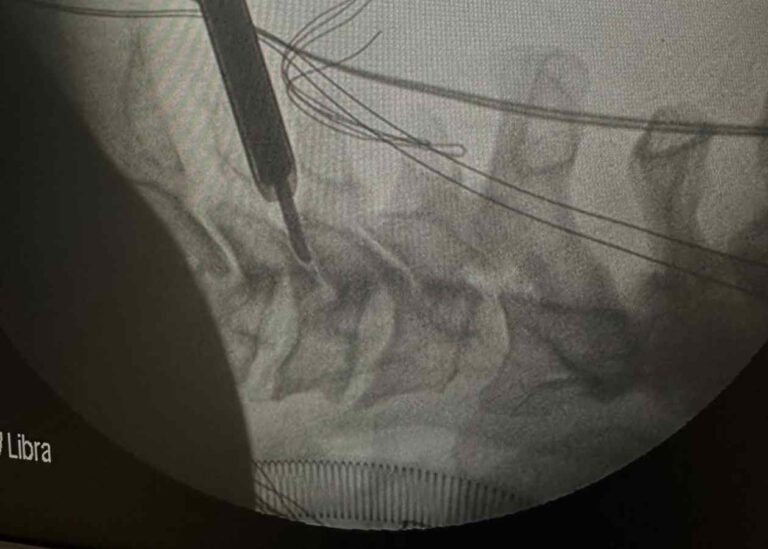

Tam Kapalı (Full Endoskopik) Boyun Fıtığı Ameliyatı Nedir? Avantajları Nelerdir?

Bel fıtığı, günümüzde özellikle masa başı çalışanlar, hareketsiz yaşam süren bireyler ve ağır fiziksel yük…